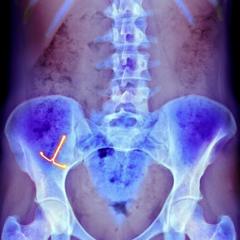

FUENTE DE LA IMAGEN,GETTY IMAGES

Mientras que los objetos que pasan por la boca representan un punto de entrada en el cuerpo, algunas personas pierden cosas por el otro extremo. Puede ser la vagina o el recto.

Los cuerpos extraños dentro de la vagina pueden ser aquellos que son médicamente necesarios y aquellos que están allí por otras razones.

Los típicos objetos extraños vaginales incluyen pesarios o dispositivos anticonceptivos intrauterinos dañados que la paciente puede haber olvidado, o que no se haya dado cuenta de que están dañados.

Estos representan riesgos a largo plazo en forma de infecciones, fístulas (una apertura anormal entre un órgano hueco y otro o entre un órgano hueco y la superficie de la piel), y la formación de cálculos.

En este extremo del cuerpo, también se han encontrado cosas dentro del ano y el recto. Entre 66% y 85% de los que llegan a urgencias con esa queja son hombres.